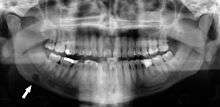

Panoramic radiographs have the capability to demonstrate a portion of the neck and display atheromas (calcifications in the carotid artery) which are an indication of both local and generalized (systemic) atherosclerosis. Atherosclerosis of the coronary arteries leading to myocardial infarction (heart attack), and atherosclerosis of the carotid artery leading to stroke are the number one and number three most common causes of death in the United States.[5]

There is interest to look at panoramic radiographs as a screening tool, however further data is needed with regards if it is able to make a meaningful difference in outcomes.[6]

Epidemiology: General Public and High Risk Groups

Additional research projects have further determined the prevalence rate of these atheromas in the general population (3-5%)[7] and among high-risk groups (over 25% in: recent stroke victims,[8] individuals with obstructive sleep apnea syndrome,[9][10] postmenopausal women,[11] type 2 diabetics,[12][13] individuals with dilated cardiomyopathy,[14] and among individuals who have received radiotherapy directed at the neck,[15][16]). These findings have been corroborated by other several other researchers.[17][18][19][20]